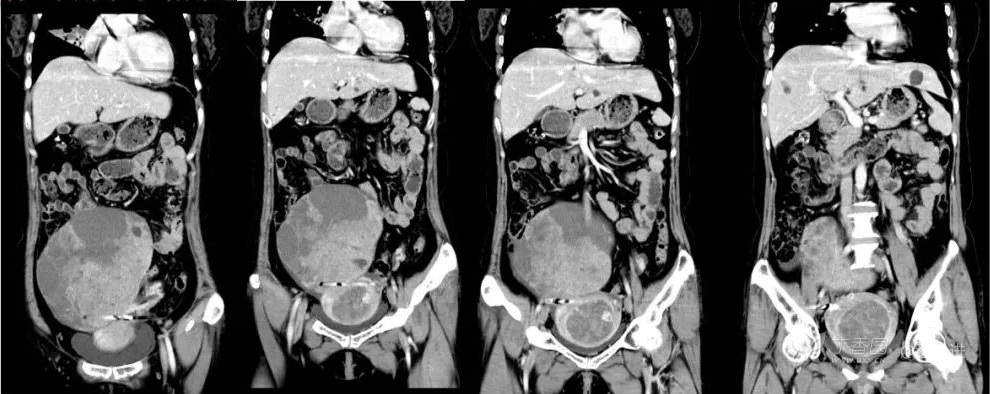

B超:中腹部混合回声肿块,性质待定